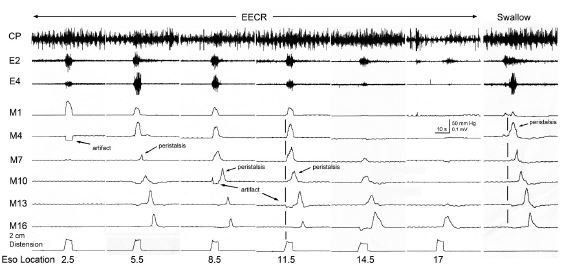

It was found that distension or contraction of the esophagus [24,29,32,35] was associated with contraction of the esophagus orad of the stimulus (Esophago-Esophageal Contractile Reflex (EECR)) and/or the upper esophageal sphincter (Esophago-UES Contractile Reflex (EUCR)), and usually followed by Secondary Peristalsis (SP). The most significant study [30] associating the slowly-adapting muscular mechanoreceptor with these reflexes was the observation that removal of the mucosal layer of the esophagus blocked all reflexes stimulated by distension of the esophagus except the EUCR, EECR, and SP (Figure 1). Considering that no other receptor had been found in the muscular layer or that anesthetizing the mucosa with lidocaine did not block SP or EUCR [30], these reflexes must have been mediated by muscular mechanoreceptors. This was further confirmed by the observations that the EUCR and SP were more readily activated by a slowly rather than rapidly applied tension to the esophageal wall and that these reflexes were not activated by stroking the esophageal mucosa [30]. Therefore, the slowly-adapting muscular mechanoreceptor mediates EUCR, EECR, and SP.

The function of these rapidly-adapting mucosal mechanoreceptors was defined by experiments which investigated the effects of removal of the mucosa from the esophagus. It was found that removal of this layer of the esophagus totally eliminated the activation of belching [30] and the reflex effects that occur during belching, but had no effect on EUCR, EECR or SP (Figure 1). These belch-related reflexes [30,34,50] are esophago-upper esophageal sphincter (UES) relaxation reflex (EURR) (Figures 1, 3, 4 & 6), Esophago-Glottal Closure Reflex (EGCR) (Figures 1 & 2), Esophago-Hyoid Distraction Reflex (EHDR) (Figures 1 & 3), and the Esophageal striated muscle Retrograde Peristaltic Response (ERPR) (Figure 4). Belching and all of these associated reflexes are activated by rapid injection of air into the esophagus [30,34,50], which correlates very well with the rapidly-adapting nature of the mucosal mechanoreceptors. In addition, belching and all of these reflexes are mediated by the vagus nerve [30,34], which is the afferent nerve of the rapidly-adapting mucosal mechanoreceptors. Therefore, the rapidly adapting mucosal mechanoreceptors mediate belching and its associated reflexes, which aid the process: EURR, EGCR, EHDR and ERPR.

Figure 1: Functions of muscular slowly-adapting and mucosal rapidly-adapting mechanoreceptors. This figure illustrates the effects of removal of the esophageal mucosa on the reflex responses activated by esophageal distension [30]. The arrows indicate the times of injection of air at listed volumes and injection rates. Removal of the mucosal layer blocked the reflexes activated by the rapidly-adapting mucosal mechanoreceptors, i.e., EURR, EGCR, and EHDR; but did not block the reflexes activated by the muscular slowly-adapting mechanoreceptors, i.e., EUCR or SP. The EURR is indicated by the decrease in CP EMG during the stimulus, EGCR by the increase in IA EMG, EHDR by the increase in GH and TH EMG, EUCR by the increase in CPEMG after the stimulus, and SP by the peristaltic wave of manometric pressure after the stimulus. The CP is the primary muscle of the Upper Esophageal Sphincter (UES). This study was conducted in an anesthetized cat.

ESO#: Esophagus #; LES: Lower Esophageal Sphincter; EMG: Electromyography; HG: Geniohyoideus; TH: Thyrohyoideus; CP: Cricopharyngeus; IA: Intraaryternoideus; CT: Cricothyroideus.

Figure 2: EECR activated by stimulation of the esophageal muscular slowly-adapting tension receptors. This figure depicts the nature of the Esophago-Esophageal Contractile Response (EECR) activated by stimulation of the slowly-adapting muscular tension receptors [35]. Distending the esophagus with a balloon at 2.5 to 17 cm from the UES activated EECR and SP. The simultaneous non-propagating contractions orad of the stimuli are the EECR’s and the propagating contractions from the point of stimulation distally are the SP’s. When the stimulus was applied at 2.5 cm from the UES, only EECR occurred. Stimuli from 5.5 to 14.5 cm caused of the UES all had both EECR and SP. The comparison of the esophageal responses during primary peristalsis of swallowing with the responses caused by stimulation of the slowly-adapting muscular mechanoreceptors clearly illuistrate the non-propagating nature of the EECR. The distending balloon sometimes caused an artifactual rapid reduction in pressure in nearby recording sites. The EECR is more likely to be activated by stimulation of the slowly-adapting muscular tension receptors of the orad esophagus. This study was conducted in the decerebrate cat.

CP: Cricopharyngeus; SP: Secondary Peristalsis; UES: Upper Esophageal Sphincter; E#: EMG Recording # cm from the CP; M#: Manometry Recording # cm from CP; Eso location: Location of the balloon from the CP.